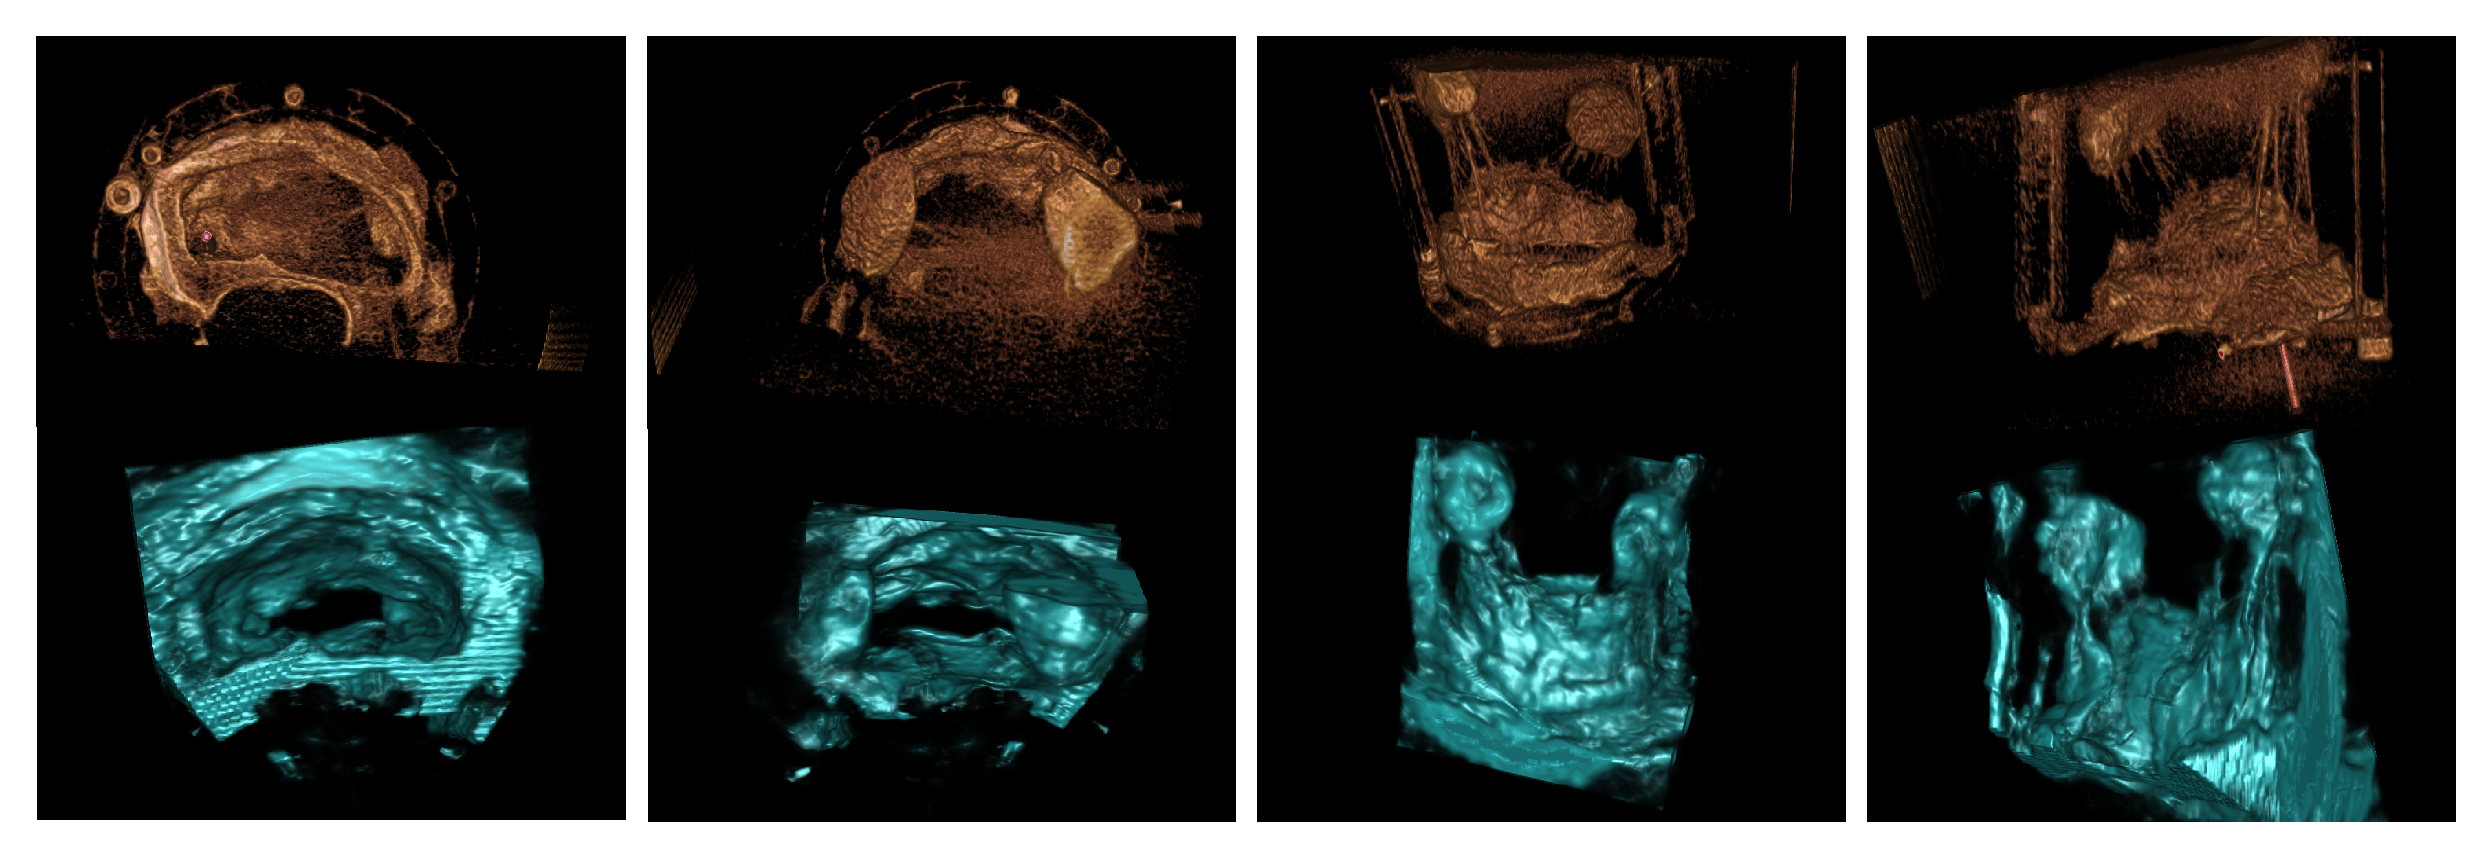

3.1. Porcine Model

3.2. Patient Images